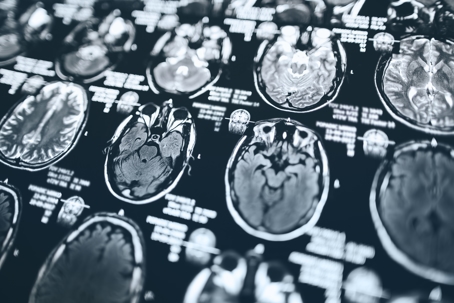

A personal injury case requires a plaintiff to prove several different elements. Perhaps the most heavily disputed are the plaintiff’s injuries and the cause of those injuries. Medical evidence can take many forms, but none is more effective than an MRI. Short for “Magnetic Resonance Imaging,” this diagnostic tool is key to diagnosing and treating your injuries and maximizing the compensation you receive in your case.

Diagnosing injuries after an accident isn’t always as straightforward as a bruise, cut, or fracture. Many injuries can’t be diagnosed just by observing a body part or conducting a physical exam. An MRI provides that needed insight by detecting hidden injuries, like spinal discs, nerves, and other internal structures.

An MRI gives medical providers a high level of detail as to exactly what your injury is and what’s causing your pain. That information allows them to create a treatment plan specific to you and your injuries.

Getting an MRI after an accident can be a critical step in ensuring you receive the proper care you need. This high-resolution imaging tool not only helps diagnose hidden injuries such as nerve damage, soft tissue injuries, and internal organ damage but also provides concrete evidence in a personal injury lawsuit later on.